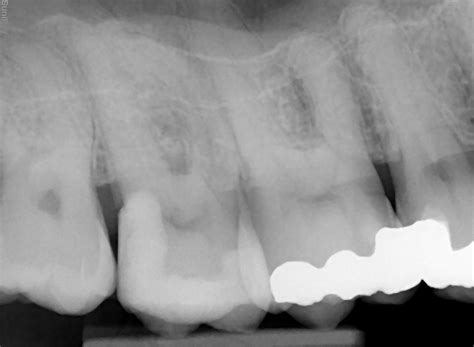

Endodontic Microsurgery - Dublin Endodontics | Endodontist Dublin